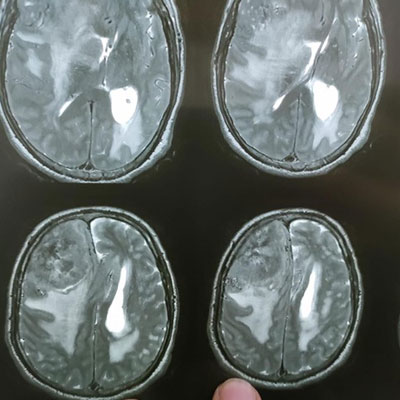

Dr. Ujwal Yeole is an experienced neurosurgeon specializes in treating a wide spectrum of neurological conditions including neuro-oncology, peripheral nerve disorders, vascular disorders, spinal pathologies, pediatric neurosurgery, neuro-trauma and skull base neuroendoscopic procedures.